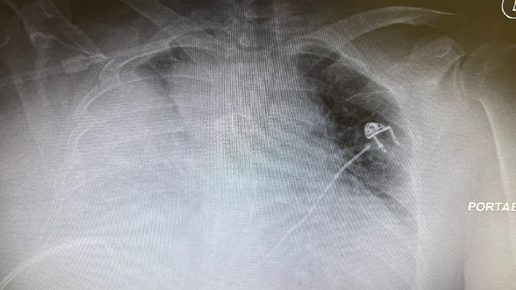

Анестезиологи - одни из самых загадочных и малоизвестных широкой публике специалистов в медицине. Они незримо присутствуют в операционных, реанимациях и родовых залах, незаметно контролируя жизненно важные функции пациентов во время наркоза. Но за рутинными манипуляциями с наркозными аппаратами и мониторами скрывается огромный пласт уникальных знаний, навыков и ежедневного риска, с которым сталкиваются эти врачи. Что же на самом деле кроется за кулисами профессии анестезиолога?

Анестезиологи работают в условиях постоянного риска и непредсказуемости...